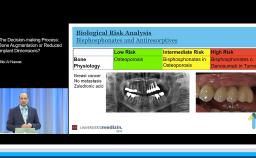

This presentation introduces and addresses the physiologic changes that occur in the oral cavity with age. Particular focus is given to the dental and periodontal tissues, oral mucosa, salivary glands, and the alveolar process (or alveolar bone). A differentiation is made between changes associated with age and those associated with pathology or therapy, particularly in regard to bone. General considerations are provided regarding treatment planning of elderly patients for dental implants.

- differentiate between physiologic changes and pathologic or therapy-induced changes

- discuss the influence these changes may have on planning for implant placement and restoration